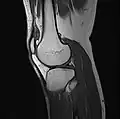

Imaging

MRI

Both anterior cruciate ligament (ACL) and posterior cruciate ligaments (PCL) are hypointense on both T1 and T2 weighted images of MRI. However, some high signal striations are often seen at the distal part of the ACL, making ACL higher intensity than PCL on MRI scans.[20]